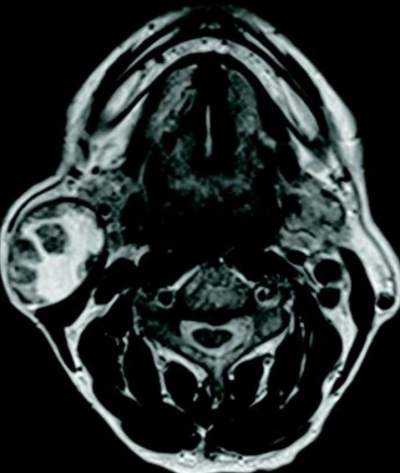

60 歳の男性。右耳下部腫瘤を主訴に来院した。1か月前、洗顔時に気付いたが痛みはなくそのままにしていたという。右耳下腺後下部に軟らかい腫瘤を触れる。穿刺吸引細胞診で囊胞性背景に胞体が好酸性の上皮細胞集塊を認める。頸部 MRIを別に示す。⁹⁹mTcO₄⁻ 唾液腺シンチグラフィで病変部に集積を認める。

T2強調像水平断像

T2強調冠状断像